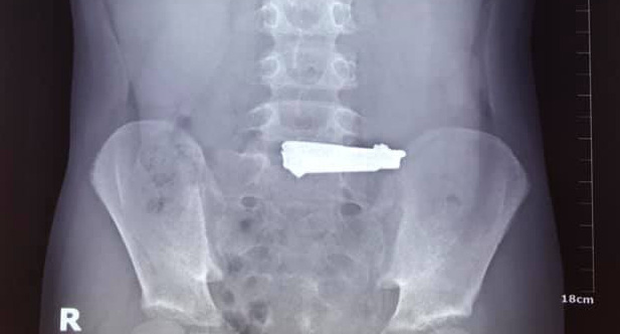

30/10/2020 19:30Bắt chước video trên YouTube, bé 9 tuổi nuốt... bấm móng tay vào bụng

Qua thăm khám và nội soi dạ dày, các bác sĩ phát hiện dị vật là một chiếc bấm móng tay có kích thước 60x16mm, nằm tại vị trí phình vị lẫn thức ăn, gây tổn thương xước niêm mạc dạ dày. Ngay lập tức, kíp nội soi tiêu hóa đã tiến hành gắp dị vật kịp thời và thành công.